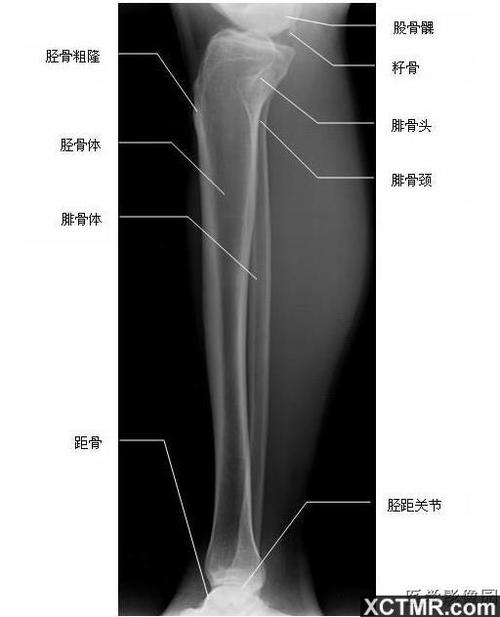

胫腓骨侧位-x线-解剖图片

填图题 | 胫腓骨解剖

胫腓骨正位—x线

胫腓骨侧位片

胫腓骨侧位图片标准

胫腓骨正侧位标准图片

胫腓骨正侧位

胫腓骨正侧位图片

正常胫腓骨x线正侧位

胫腓骨解剖

胫腓骨解剖图